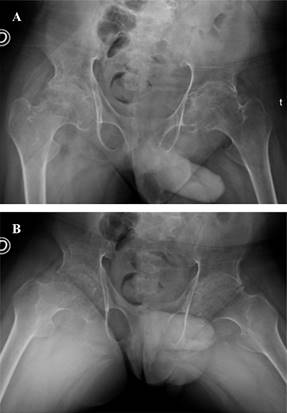

Radiográficamente presentaba coxartrosis bilateral, con pobre calidad ósea y un fémur proximal tipo Dorr C (Figura 1). Además, presentaba camptodactilia, platispondilia, discopatías, disminución de la luz articular y ensanchamiento episario en ambas rodillas (Figura 2). El análisis de laboratorio no presentaba alteraciones en marcadores inflamatorios, ni ningún otro tipo de alteración.

Figura 1: A y B) Radiografías anteroposterior y Lowenstein de ambas caderas. Se aprecia la afección articular bilateral, la pobre calidad ósea y el Dorr tipo C en fémur proximal.